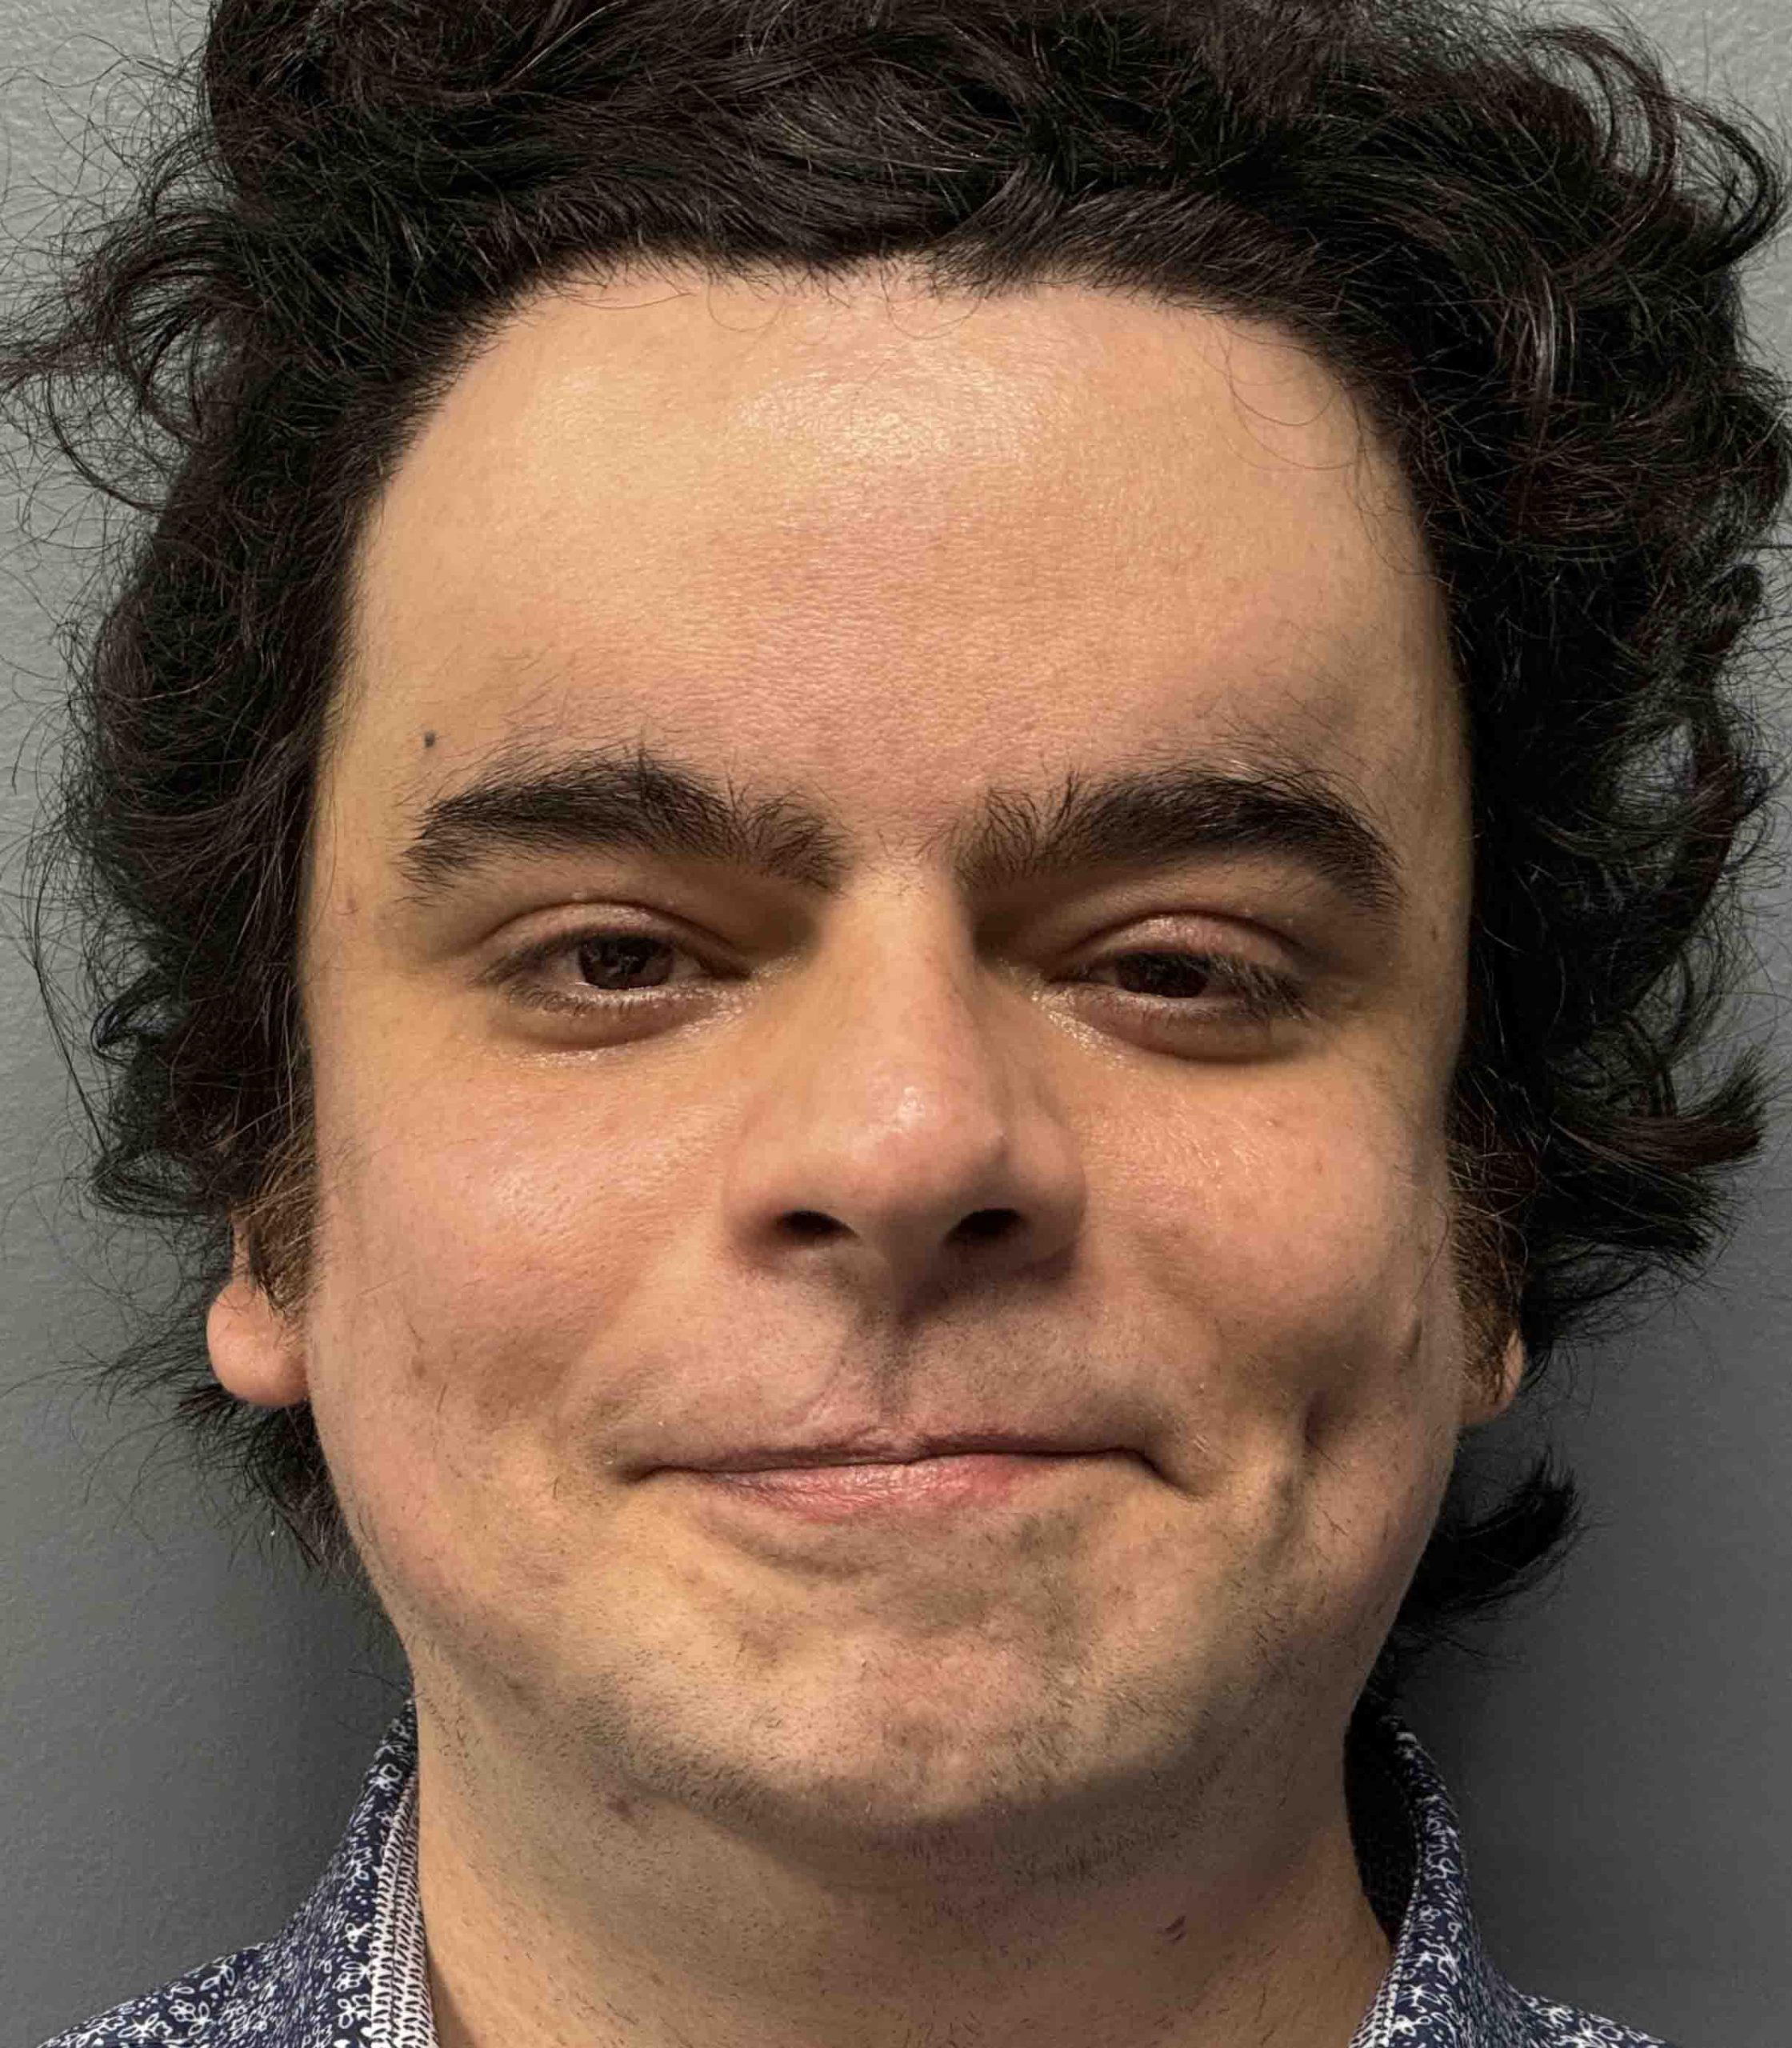

Patient 7

Desire to correct dents on his skull and give a rounder head shape.

Placement of custom skull implant to fill in bilateral parietal skull defects and create a rounder head shape.

Desire to correct dents on his skull and give a rounder head shape.

Placement of custom skull implant to fill in bilateral parietal skull defects and create a rounder head shape.